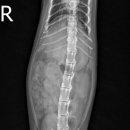

근처 목동근처에 로운동물병원이 있어서 전화예약을 하고 가게 됐는데, 그 전에 우선 부천 병원에 먼저 가야합니다 이유는? 수술을 받은 곳에서 수술이 잘 된 걸 확인해야 하고 (타 병원에서는 수술을 자기 병원에서 하지 않았을 때 문제가 생기면 책임 질 수 없기 때문이라는 겁니다) 복잡하지요.... (등에 있는 건...